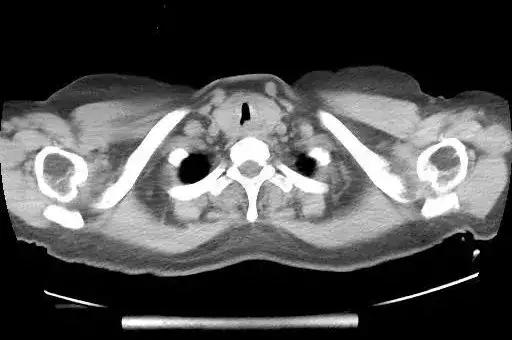

近 3 月痰中带血,伴喘憋加重,行胸部 CT 提示左侧杓会厌皱襞、双侧声带、室带、前联合、气管上段可见软组织增厚影及软组织团块影,考虑良性病变可能大。

患者喘憋、呼吸困难明显,结合胸部CT可见患者声门下管腔明显狭窄,管壁增厚,术中需在保证通气的情况下解除气道梗阻。术中可考虑切割或切除部分增厚的气管粘膜。